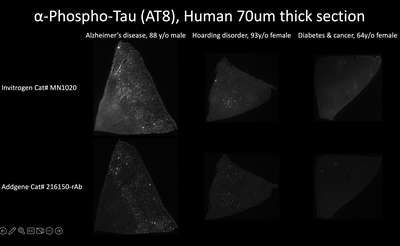

#216150-rAb

Anti-MAPT (Human) recombinant mouse monoclonal antibody; recognizes the disease-associated version of Tau (phospho-Tau)

Immunohistochemistry

Reactivity

Human